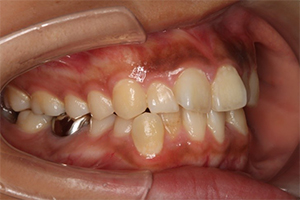

矯正治療のCASE 02

Before

After

- 主訴

- 上顎前歯が出ていて口が閉じにくい

- 治療内容

- 上顎前突・出っ歯の非抜歯による歯並び治療

- 治療費用

- 88万円~(税込)

- 治療期間

- 12ヶ月

【リスク・副作用】

歯の痛み、口内炎、歯磨きがしにくいことによるむし歯や歯周病のリスク、歯根吸収や歯の変色、後戻りなどの副作用があります。